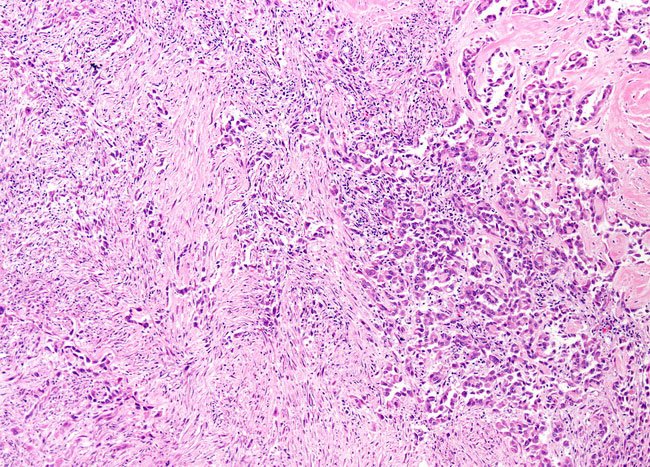

Biphasic mesothelioma is a cancer characterized by a mix of epithelial and sarcomatoid cells. To be classified as biphasic, the biopsied sample must contain more than 10% of either epithelioid or sarcomatoid cells.

Biphasic mesotheliomas are tumors that include a mix of these two cell types. Epithelial cells make up tissue in the body that lines the surfaces of organs, blood vessels, and the interiors of cavities. When these cells become cancerous, it is called a carcinoma.[4]

On the other hand, sarcoma develops from cells that make up bone, fat, muscle, vascular, and connective tissue. Sarcomas are rarer than carcinomas. [4]

- Epithelioid cells appear as rounded, cube-like shapes.

- Sarcomatoid cells are spindle-shaped and arrange themselves in a disorganized manner.